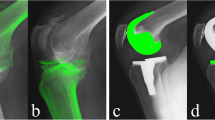

The most important finding of the present study was that BB in noncontact ACL injuries seems to occur with flexed knee (average 46°), a significant amount of anterior and proximal translation of the tibia, and mainly in external rotation and valgus. In all BB models, the tibia appeared evidently sub-luxated anteriorly. This condition became more evident when compared to Dynamic RSA at the same knee flexion angles (Fig. 4). Moreover, knee kinematics during an active flexion–extension did never reproduce the BB mechanisms.

Comparison of knee position at BB genesis (a) and during squat for the same flexion angle of BB genesis (b). Notice the significant amount of tibial anterior and proximal translation in the first figure with respect to the knee position and orientation observed in the execution of a physiological motor task, reflecting the idea that BB genesis could occur during a knee locked sub-luxation